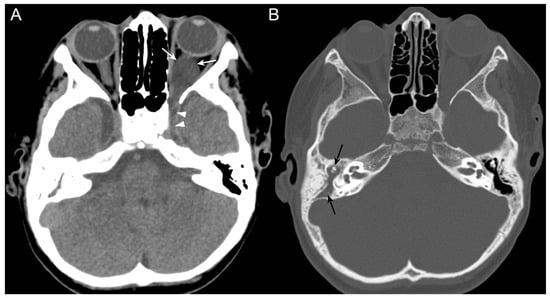

3.1. Case Report